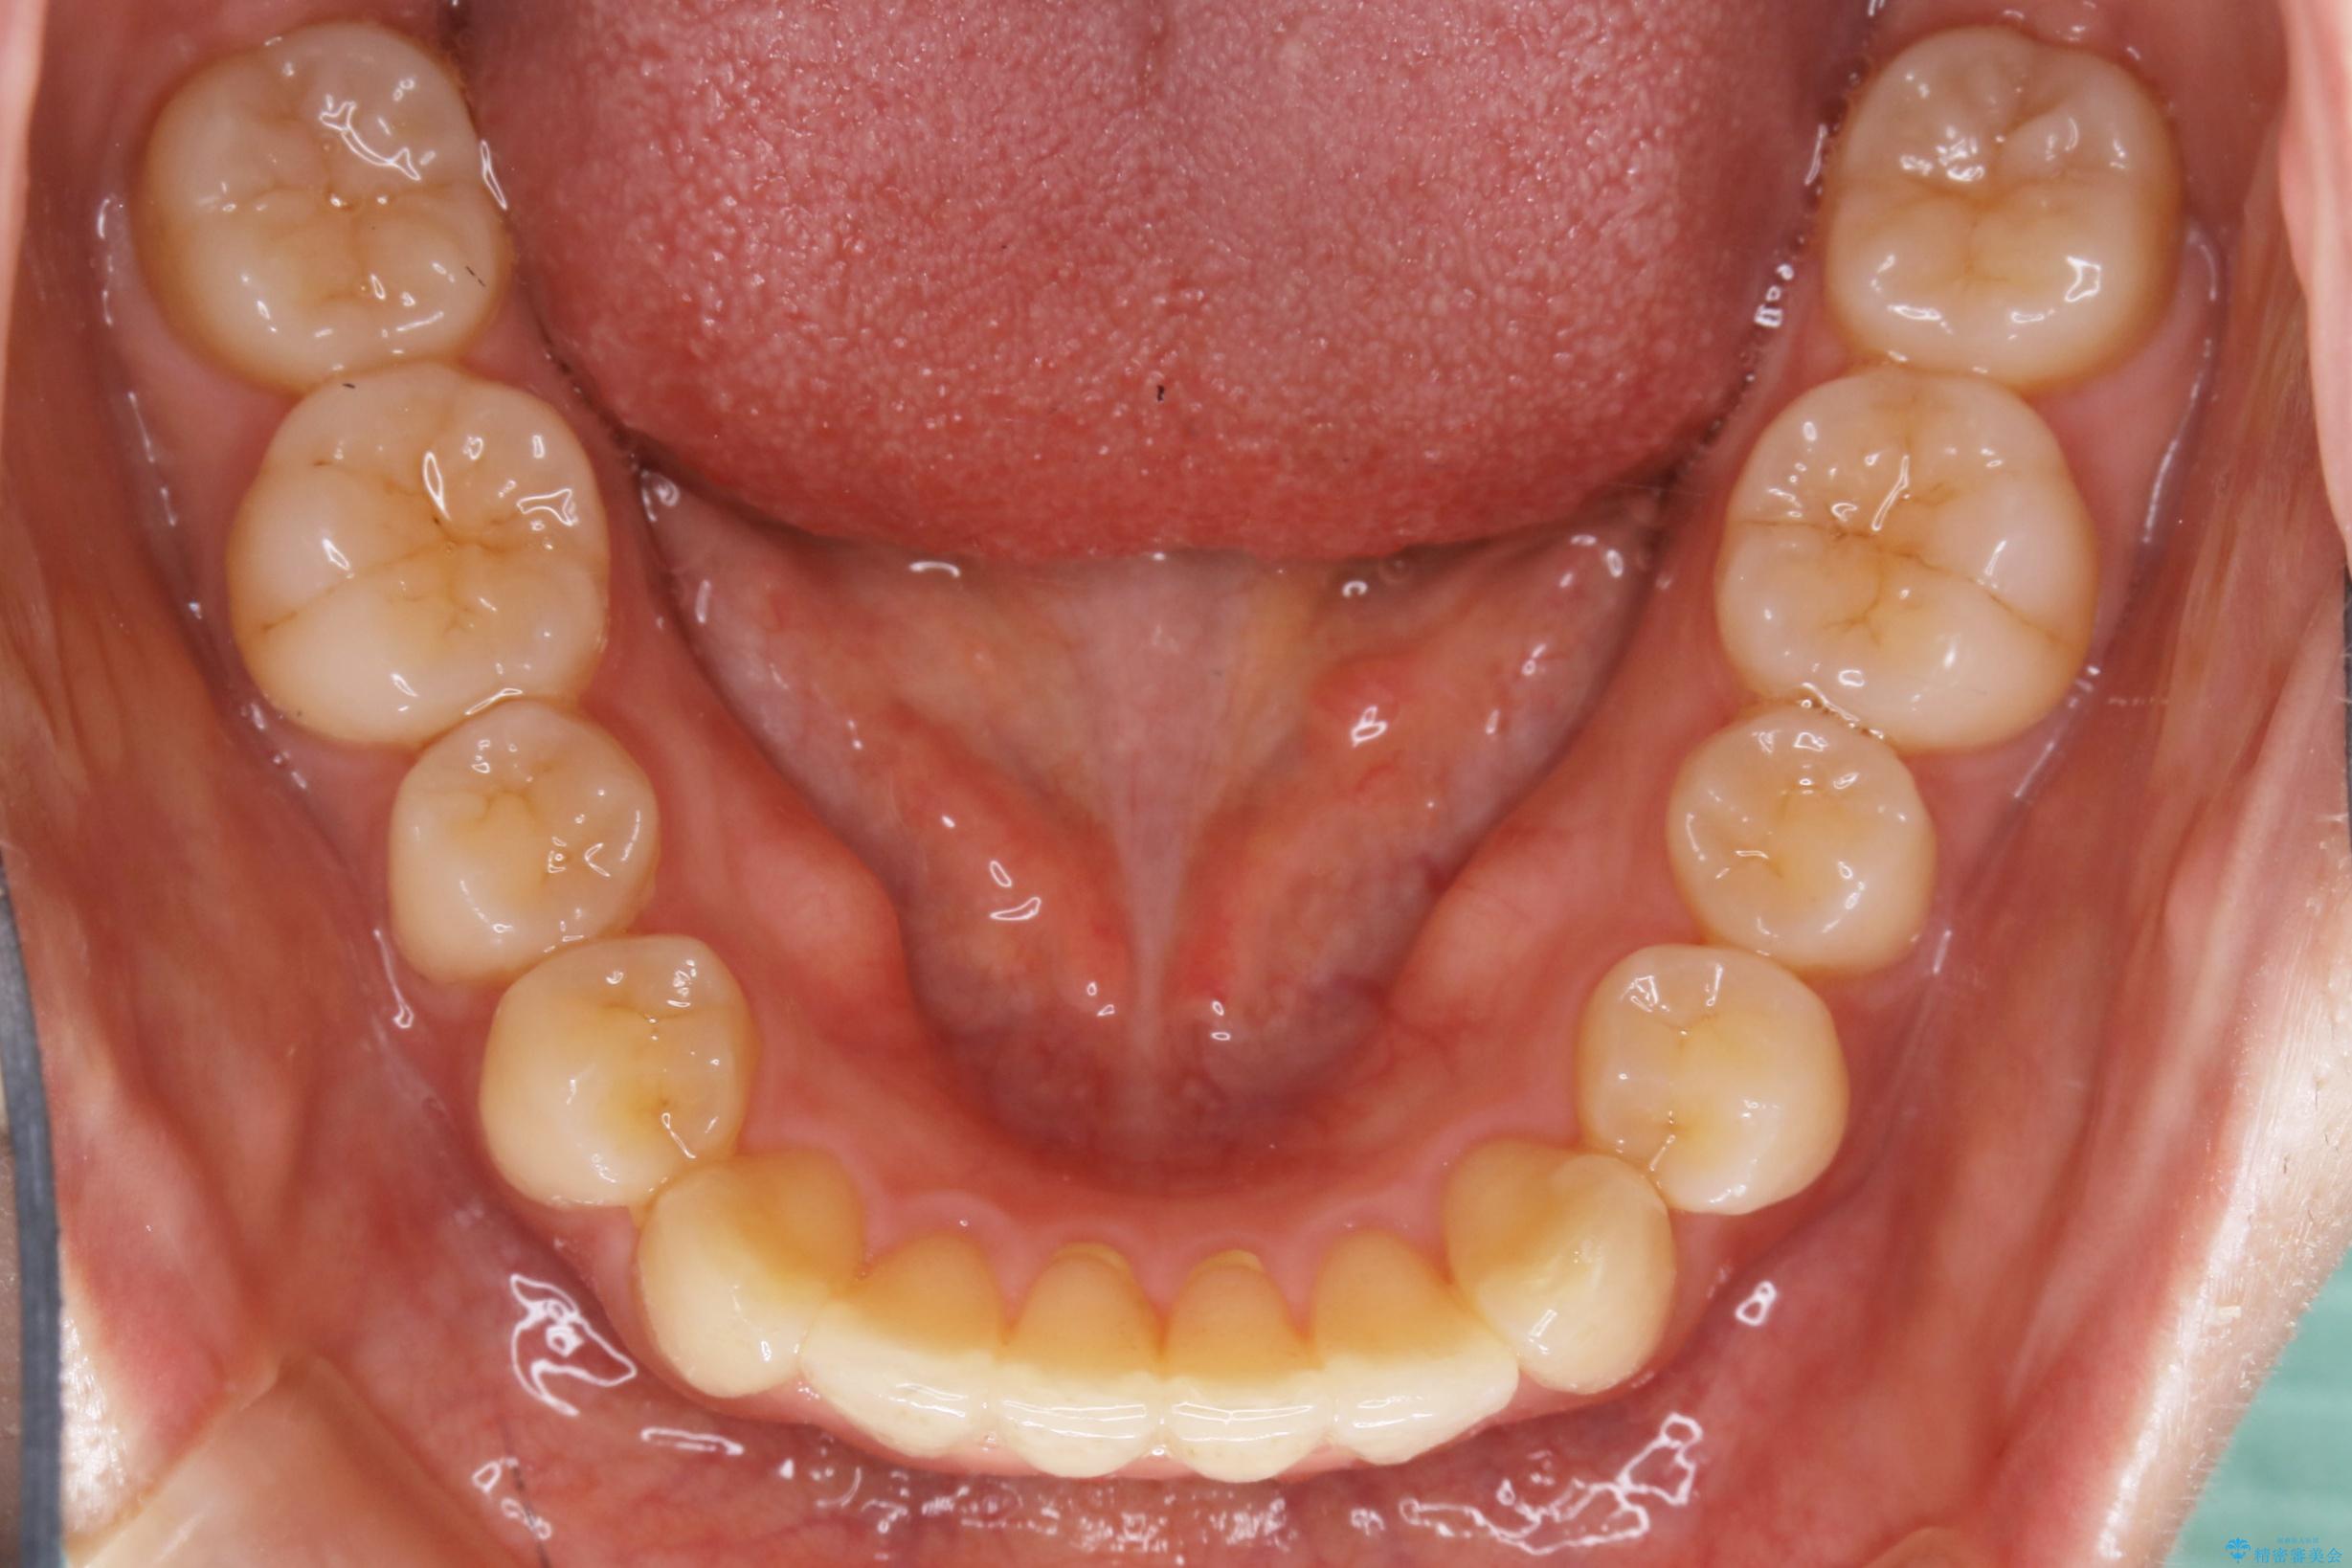

下の前歯のガタつきが気になるとご来院された患者様です。

インビザラインのライトパッケージにて、歯列拡大とディスキング(IPR)をを行いスペースをつくり非抜歯で治療を行いました。

歯並びが悪くなる原因の一つに「歯列弓の狭窄」というものがあります。

奥歯や前歯が内側(舌側)に倒れ込んでしまったり、歯が生えてくる位置が内側になってしまうことにより歯並びのアーチが狭くなってしまうことを言います。

このような場合、歯並びのアーチを拡大してあげるだけでもガタつきを無くすためのスペースがかなり作れることがあります。